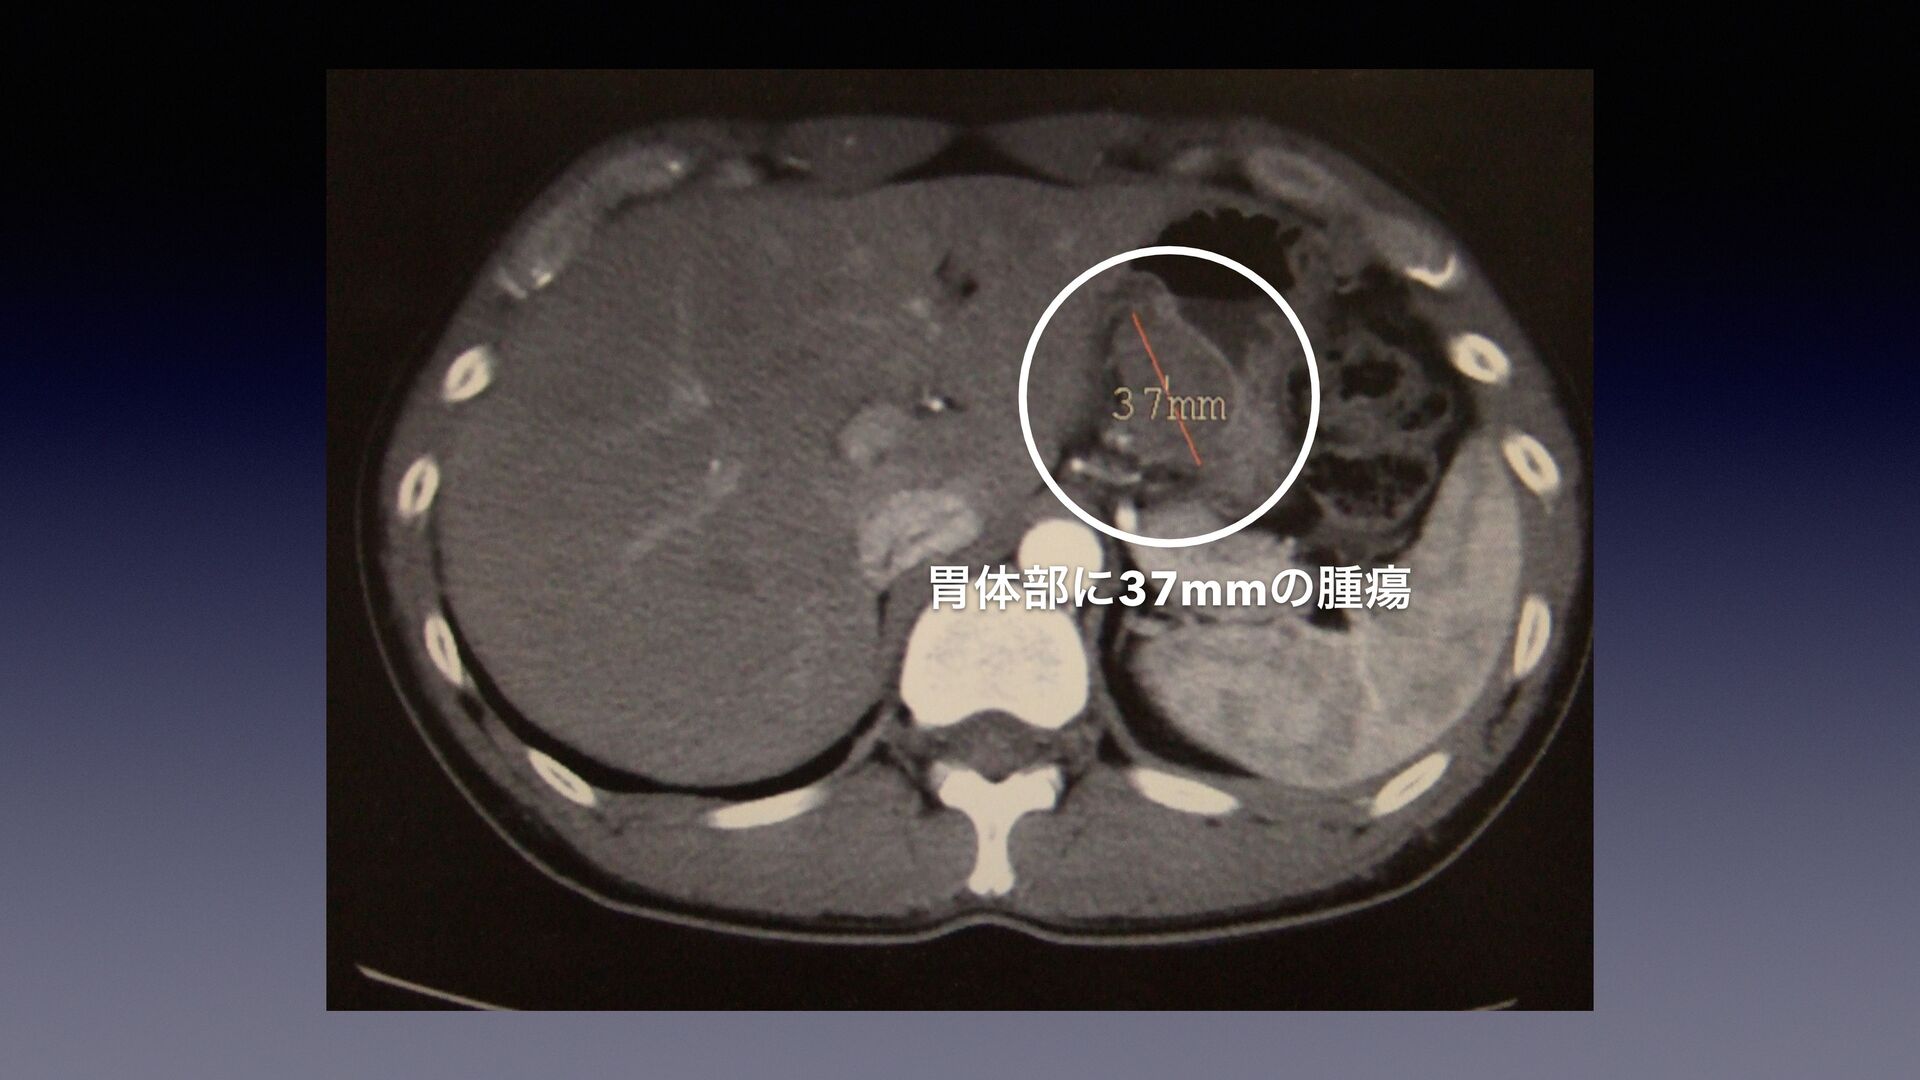

ңମ෦ʹ37mmͷजᙾ

ࢮ͵ʁ ߅͕Μࡎʁ खज़ʁ ͓ۚʁ ࣄʁ ਓੜʁ োʁ ੍ݶʁ Ոʁ